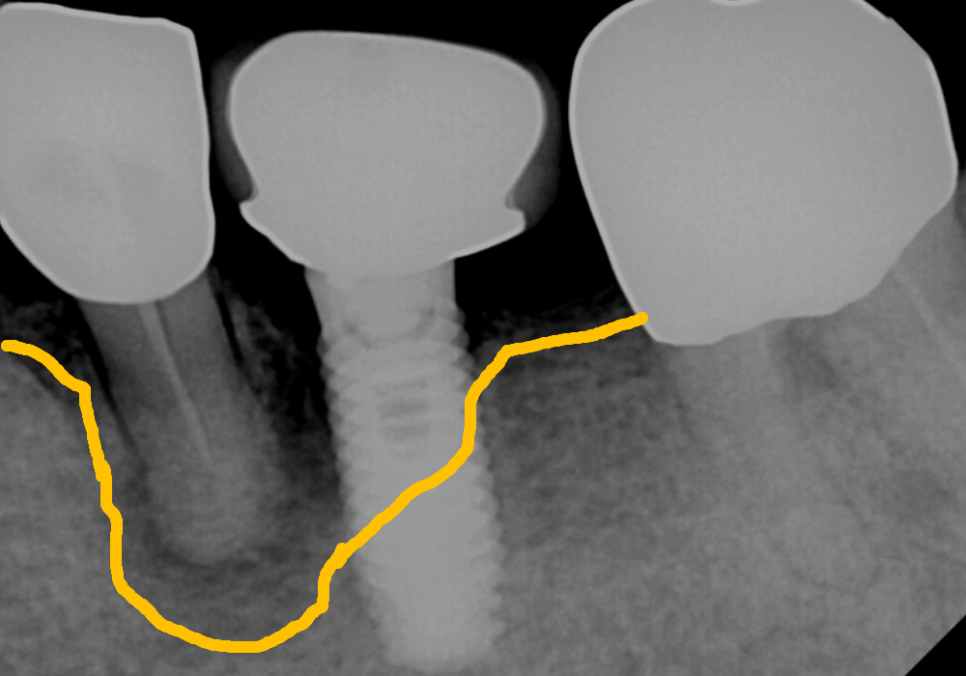

방사선 사진을 살펴보니,

자연치아 주변의 뼈가 까맣게 녹아내려 있었고,,

그 염증이 바로 옆 임플란트 주변 뼈까지

군데군데 녹이고 있는 상황이었습니다.

음식물이 지속적으로 끼고 관리되지 않으면서

염증으로 인해 잇몸뼈가 점점 녹은 상태...

흔들림이 너무 심한 자연치아는

안타깝지만 발치를 하기로 결정했습니다.